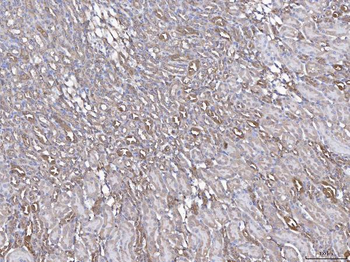

10 μg, 100 μg - Anti-CD44 Antibody [orb402179]

ELISA, FC, ICC, IF, IHC, IHC-Fr, WB

Human, Mouse, Rat

Rabbit

Polyclonal

Unconjugated

10 μg, 100 μg - Anti-PRDM1/Blimp1 Antibody [orb402200]